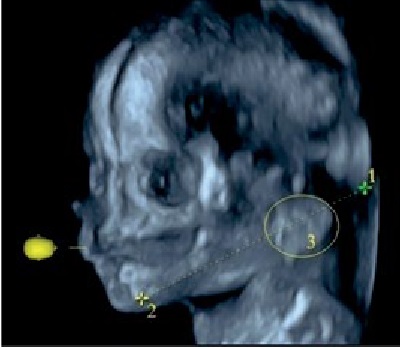

Возрастной период | Схема изменений топографических взаимоотношений ушной раковины плодов относительно нижней челюсти | Ультразвуковая сканограмма головы плода |

14–18 недель | Возраст 14 недель, пол мужской | |

19–23 недели | Возраст 21 неделя, пол женский | |

24–27 недель | Возраст 26 недель, пол женский |

Примечание. 1 – наружный затылочный выступ; 2 – гнатион; 3 – ушная раковина.

Методом ультразвукового сканирования можно изучить топографию, форму, структуры ушной раковины плода [13]. В исследовании использовались два режима: поверхностной реконструкции и костный (рисунок 1). Во всех случаях определяется условный центр ушной раковины. В костном режиме отчетливо визуализируются костные структуры, в режиме поверхностной реконструкции можно оценить форму ушной раковины и детали строения: завиток, противозавиток, козелок, противокозелок, мочку уха. Форма ушной раковины у плодов вариабельна (таблица 1).

Примечание. 1 – центральная часть ушной раковины; 2 – гнатион.

Рисунок 1. Ультразвуковая сканограмма головы плода. Возраст 20 недель, пол мужской. А – режим поверхностной реконструкции; Б – режим скелетный.

Figure 1. An ultrasound scan of the fetal head. 20 weeks old, male. A – a surface reconstruction mode; B – a skeletal mode.